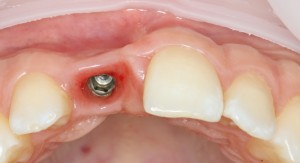

Первым делом, необходимо определиться с подготовкой лунки под имплантат. Проверить правильность позиционирования лунки можно с помощью аналогов имплантов, входящих в комплект XiVE Dentsply Implants:

Напомню, что при правильном позиционировании импланта в области фронтальных зубов, он прилегает к небной стенке лунки, а его ось выходит на небную поверхность будущей коронки. В крайнем случае, на режущий край.

Имплантат по объему всегда меньше, чем сам зуб:

Поэтому у нас возникает вопрос заполнения «пустого» пространства между вестибулярной стенкой лунки и поверхностью импланта. И, как ни странно, с Bio-Oss Collagen это удобнее сделать до установки имплантата.

Графт адаптируется (с помощью скальпеля), устанавливается в нужное положение. Для этого, опять же, очень удобно использовать аналоги имплантов из имплантологического набора (в крайнем случае, остеотомы или пины параллельности):